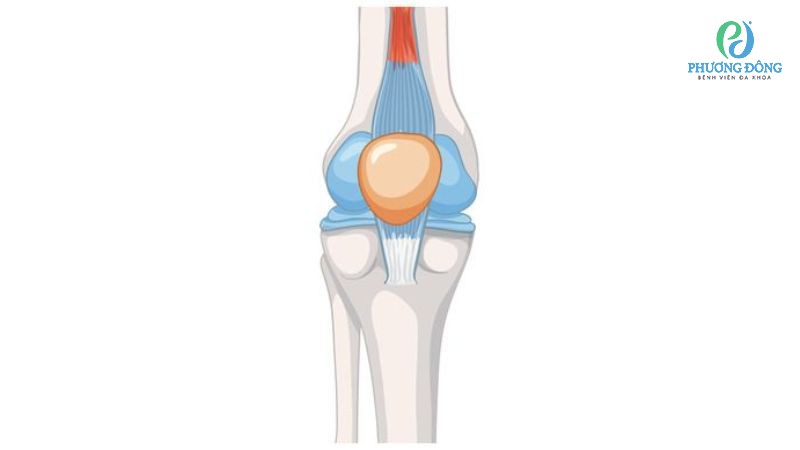

Khớp gối được coi là khớp lớn nhất của cơ thể, chứa tới 11 - 13 bao hoạt dịch. Chúng nằm phân bổ xung quanh xương bánh chè, gân cơ tứ đầu đùi, gân cơ bán gân và một số vị trí khác.

Khớp gối có tới 11 - 13 màng hoạt dịch

Màng hoạt dịch ở khớp gối đóng vai trò như chất bôi trơn, giúp chuyển động khớp gối trở nên mượt mà hơn. Bộ phận này còn được coi như miếng đệm chống sốc, giảm lực tác động lên xương ống chân khi thực hiện các hoạt động chạy nhảy.